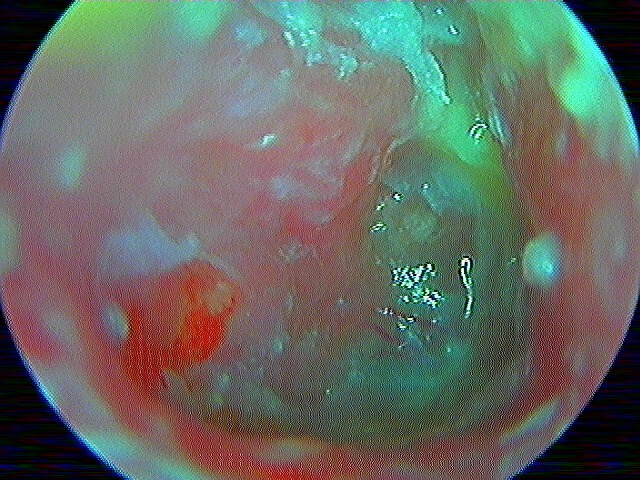

Bombement , épanchement rétrotympanique purulent jaune vif, inflammation globale; avec le cas particulier de la myringite bulleuse (virale).

MYRINGITE BULLEUSE VIRALE (chercher la bulle, souvent chez l'adulte, très douloureuse en décubitus, perfore la nuit, otorragie)